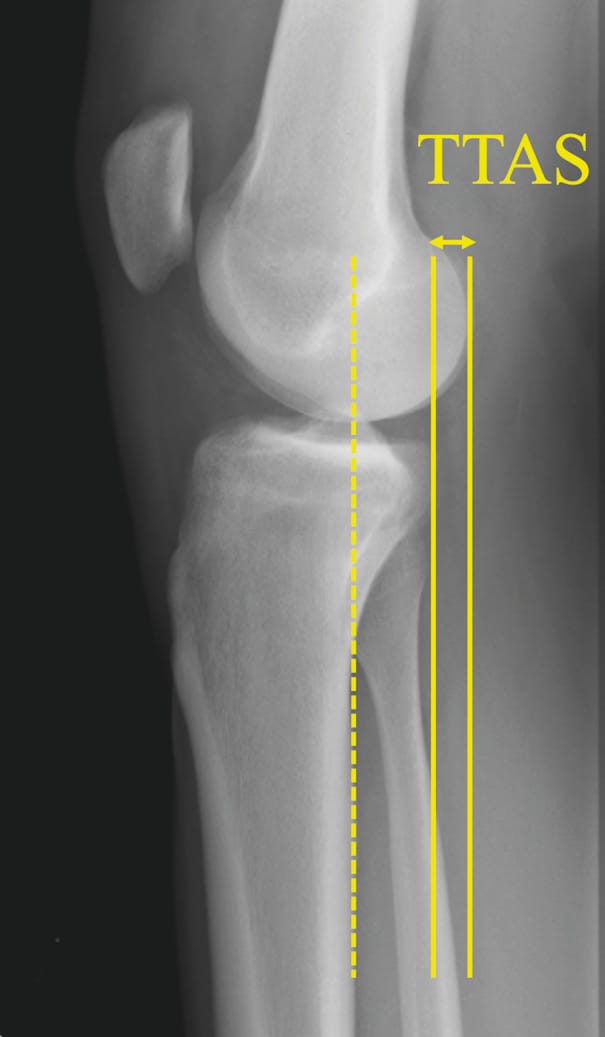

Radiology images should be obtained to include true lateral views showing 15 cm of proximal tibia with 20° of flexion in single-leg weight-bearing. The condyles will be aligned under fluoroscopy before the conventional radiography is performed. Any deviation from lateral will lead to distortions and the measurements will not be possible to interpret [14] Vieider RP, Mehl J, Rab P, Brunner M, Schulz P, Rupp MC, et al. Malrotated lateral knee radiographs do not allow for a proper assessment of medial or lateral posterior tibial slope. Knee Surg Sports Traumatol Arthrosc. 2024;32(6):1462–9. (Figure 1). Next, the technique for measuring the tibial slope must be chosen so that it is reproducible and can be compared from one study to another. It is crucial to choose one method and stick to it. The technique that uses the proximal anatomical tibial axis has a normal value of 9° of slope and the method is described in Figure 2 [15] Brazier J, Migaud H, Gougeon F, Cotten A, Fontaine C, Duquennoy A. Evaluation of methods for radiographic measurement of the tibial slope. A study of 83 healthy knees. Revue de chirurgie orthopédique et réparatrice de l’appareil moteur. 1996;82(3):195–200. . The normal value for SATT is 1.31 mm [16] Cance N, Dan MJ, Pineda T, Demey G, Dejour DH. Radiographic Investigation of Differences in Static Anterior Tibial Translation With Axial Load Between Isolated ACL Injury and Controls. Am J Sports Med. 2024 Feb 1;52(2):338–43. . If translation is posterior, the measurement will have a negative value. The measurement method is described in Figure 3.